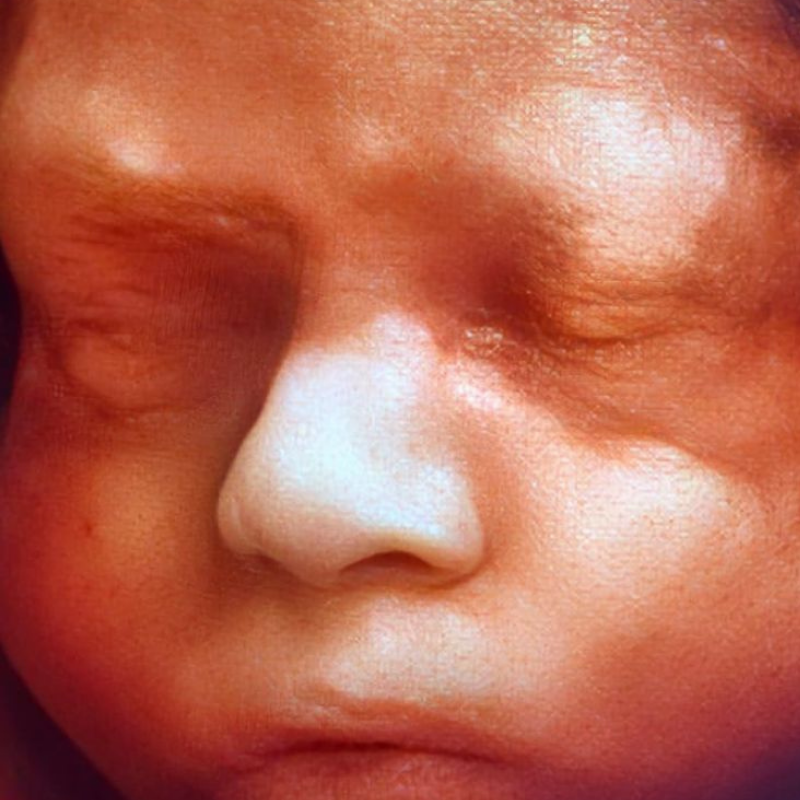

Ecografía del corazón fetal en 4D

- Las formas nuevas de ecografía pueden proporcionar imágenes en 5-D.